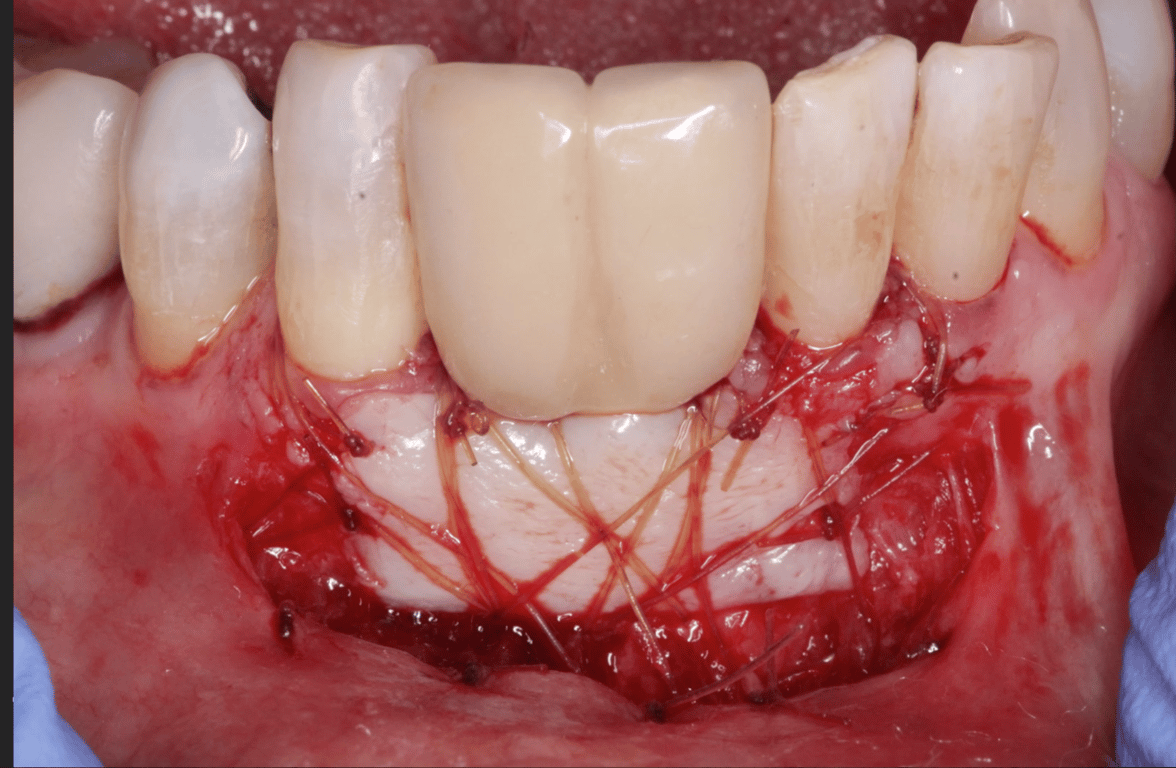

I am feeling really humble. I’ve placed multiple implants and thinking this should be a straightforward case. I was wrong. I know it’s poorly planned and freehand did not go well. Are these restorable? Should I explant and redo? If I do remove these, how easy is it to remove these?